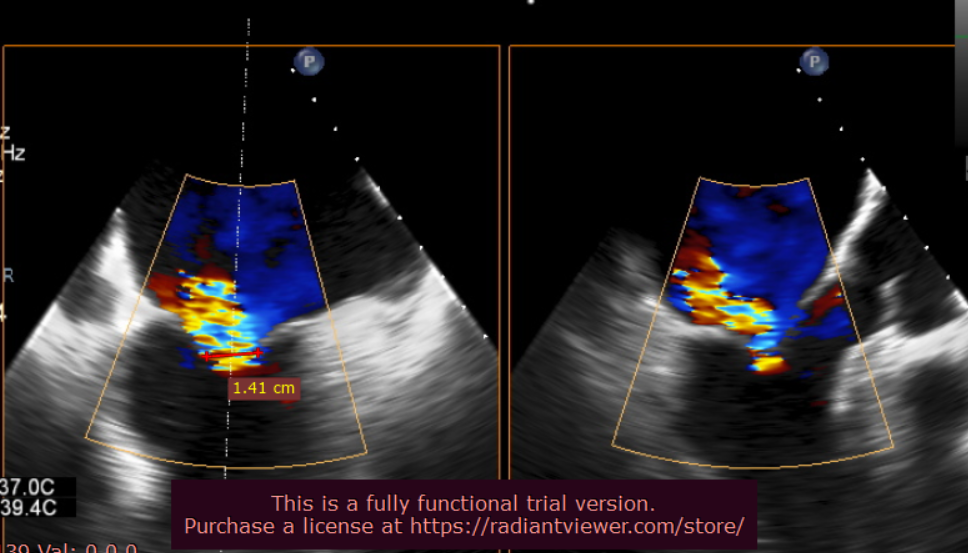

北部战区总医院心内科团队成功完成全新经股静脉缘对缘瓣膜修复系统 全国多中心临床研究首例植入手术